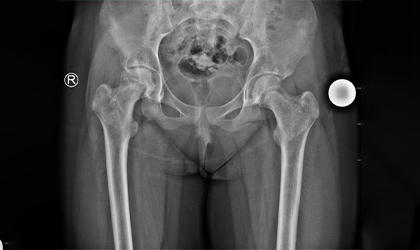

Bilateral Hip Recovery

This 34 year old medical representative had avascular necrosis with collapse of both her hips